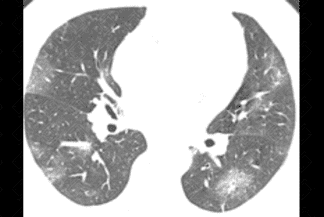

Descrição das figuras 9 e 10: Tomografia de tórax evidenciando opacidades em vidro fosco arredondadas, predominando na periferia dos pulmões, com acometimento estimado em 25% (setas vermelhas).

Interessante acrescentar que a tomografia computadorizada do tórax tem se mostrado um bom método para estimar extensão de doença . Grosseiramente, estimamos em acometimento inferior a 25% , entre 25-50% e superior a 50% .